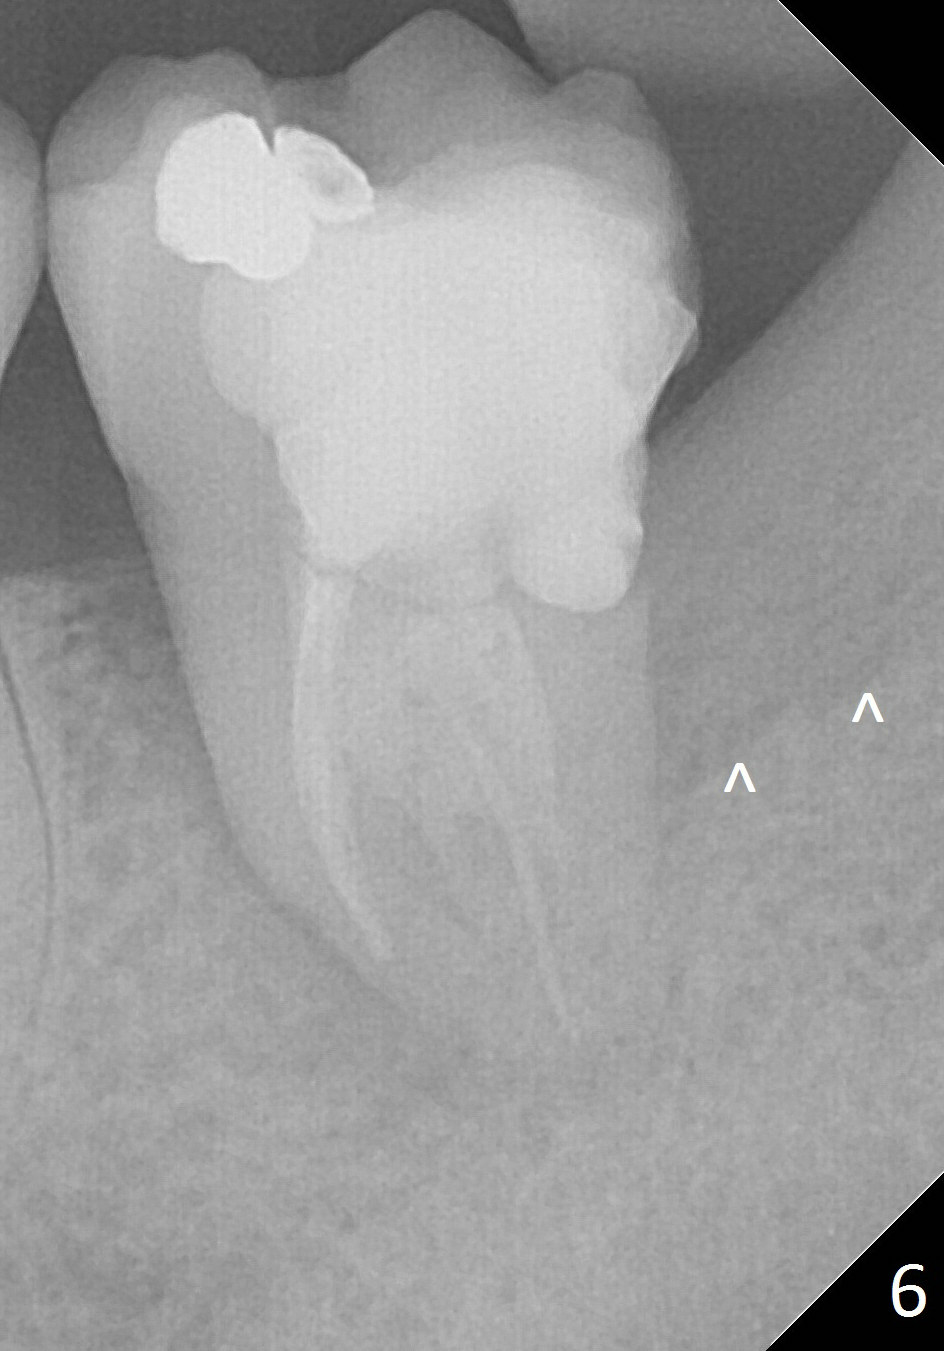

In fact, RCT is tried. Fourteen months later, the tooth remains symptomatic with mobility (Fig.6). Due to the distal defect caused by the 3rd molar (Fig.6,7 arrowheads), the implant should be placed as mesial and deep as possible.